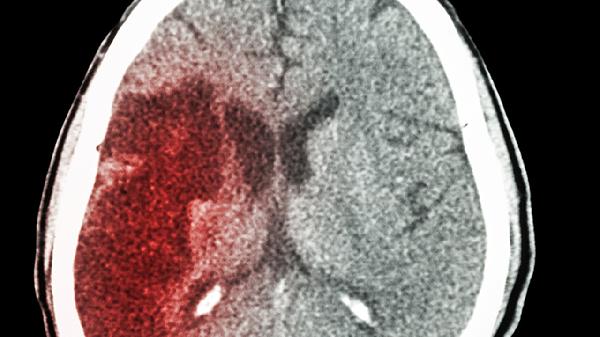

脑出血后血压增高如何解决

脑出血后血压增高可通过控制原发病、调整生活方式、药物治疗、监测血压、手术干预等方式解决。脑出血后血压增高可能与颅内压升高、应激反应、疼痛刺激、自主神经功能紊乱、高血压基础疾病等因素有关。